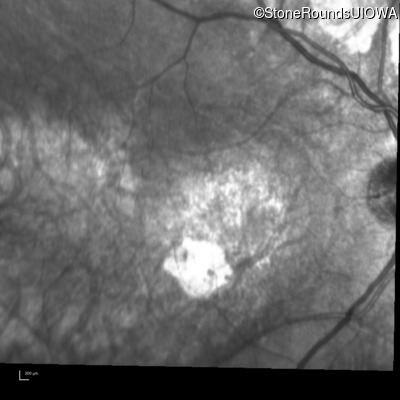

Infrared Fundus Photograph - Right - 20/100

Exemplar